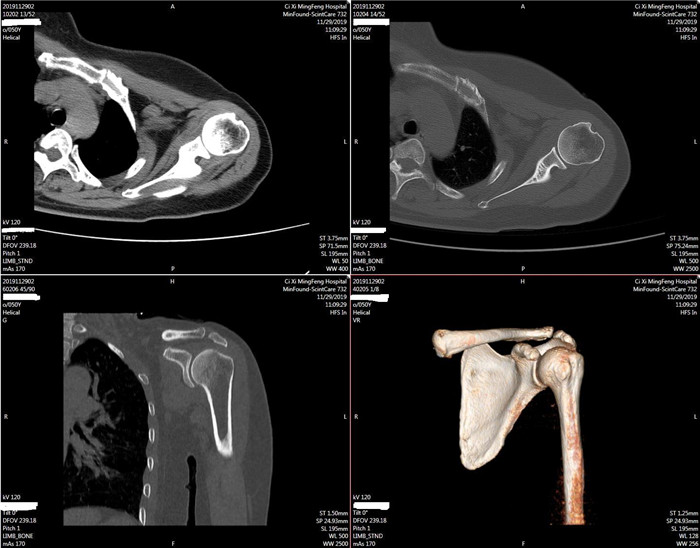

明峰CT搭載了領先的硬件技術平臺及系統,強大的掃描能力可滿足臨床的各種要求,呈現更極致的細節,為各臨床科室提供高品質的圖像。薄層掃描,消除部分容積效應,提高各向同性。配合高分辨率算法,有助于細微結構和形態學顯示。